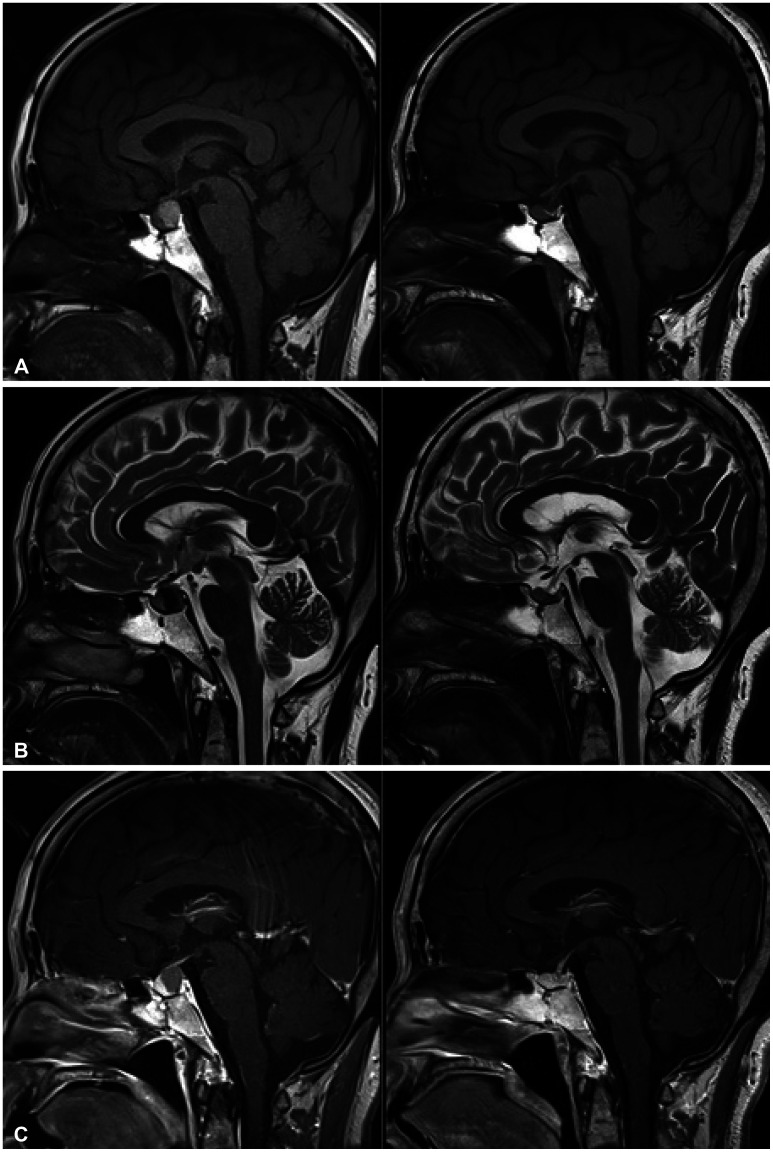

Results: PI size increased in 33 of 245 patients. For the remaining 212 patients, PI size decreased or stayed unchanged. Of the 33 patients with PI size progression, ten underwent surgery. Stalk deviation (p<0.001) and lesion enhancement (p=0.001) were significantly more observed in those with PI size progression than in those without PI size progression. MRI morphological factors were not related to changes in PI size in the presumptive Rathke's cleft cyst group. In the presumptive pituitary adenoma group, absence of tumor enhancement (p<0.001) and stalk deviation (p<0.001) were significantly associated with tumor reduction and progression, respectively.

Conclusion: Our findings support an additional guideline for patients with asymptomatic non-functional PI without stalk deviation and enhancement. For these patients, the clinical and neuroradiological follow-up periods could be reduced.